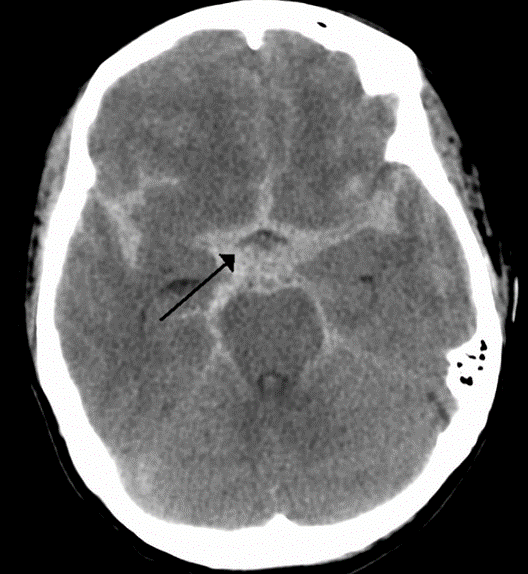

- Chẩn đoán loại tai biến: nhồi máu hay xuất huyết

Chẩn đoán loại tai biến

- Nhồi máu: 80% – 85%

- Xuất huyết: 15-20%

Chắc chắn nhờ xét nghiệm hình ảnh: CT

Chẩn đoán dễ dàng bằng CT